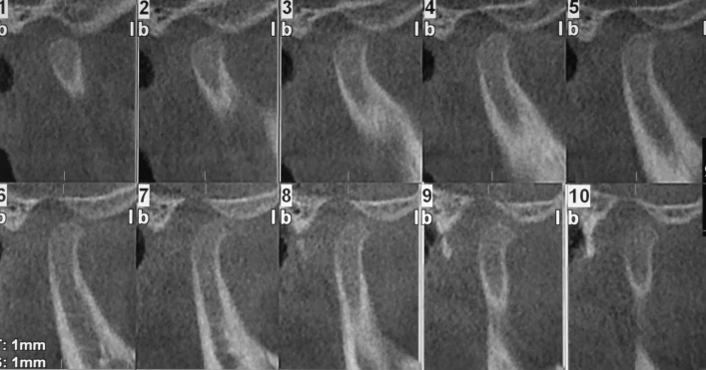

Tomografía Cone Beam Inicial

Evidencia tomográfica de la rápida evolución de la hiperplasia condilar